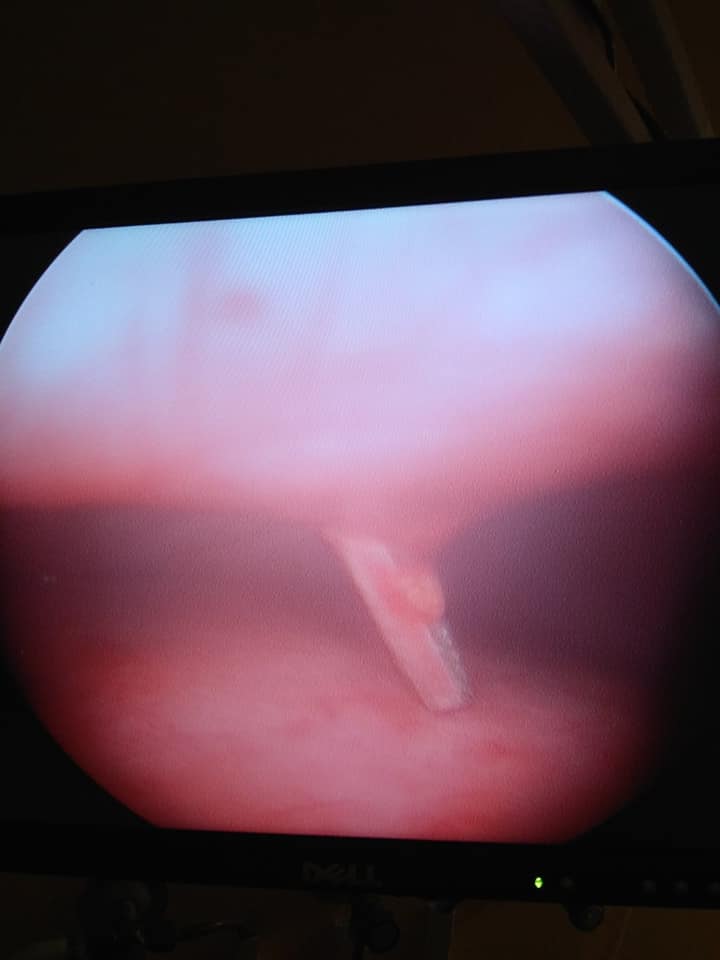

“Ми застосували найновішу сучасну методику лікування – торакоскопію. Тобто та видалення цвяха з грудної клітини. Ми дістали цвях без жодних розрізів, локалізація цвяха це дозволяла“, – розповів дитячий торакальний хірург “Охматдиту” Олег Ленів.

На серії рентген-знімків лікарі побачили будівельний цвях у ділянці лівої легені.